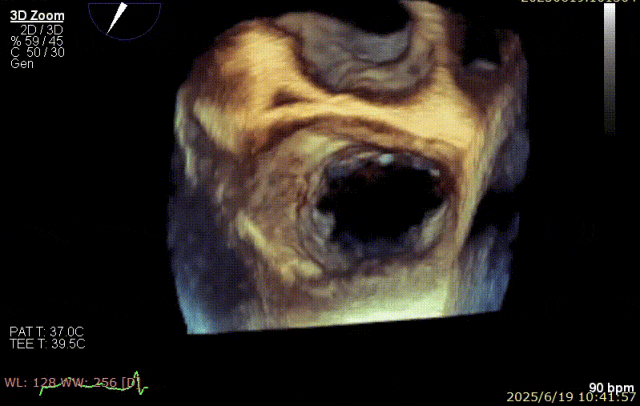

2025 年 6 月 29 日,经过对术前超声和 CT 影像进行深入分析,团队制定了周密手术计划。在麻醉手术中心副护士长刘菊梅的充分术前准备和中国医学科学院阜外医院欧阳文斌教授的指导下,凭借团队的紧密协作和娴熟操作,单纯利用超声影像精确引导,通过导引导管系统经右胸、右房,穿房间隔,建立到达左房通路;经该通路将两枚二尖瓣钳夹成功植入二尖瓣病变部位进行夹持,夹合器位于 3 区及部分 2 区,固定好,运动协调,瓣叶启闭灵活,瓣口轻度反流,二尖瓣平均跨瓣压差 2 mmHg。手术圆满完成。

手术步骤

器械植入后二尖瓣 AP 径约 35 mm,CC 径约 39 mm;夹合器固定好、组织桥稳定,前瓣夹闭后瓣叶长度 25 mm,后瓣夹闭后瓣叶长度 7 mm;二尖瓣开放好,瓣口呈大小双孔,二尖瓣瓣口面积约 2.8 cm²,平均压差 1 mmHg,关闭可,二尖瓣反流明显减轻(从术前反流 4+显著改善至 1+),手术全程无需体外循环支持,无需输血,无需射线全超声引导。患者术后第二日回普通病房,患者恢复良好,术后第五日即出院。